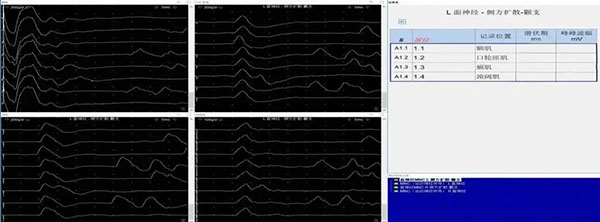

典型应用:面肌痉挛患者评估

侧方扩散现象(Lateral Spread Response, LSR)评估面肌痉挛微血管减压术患者术前LSR波引出情况,检查额肌,口轮匝肌,颏肌,颈阔肌自发放电与诱发反应。与梅杰综合症等疾病,进行鉴别诊断。